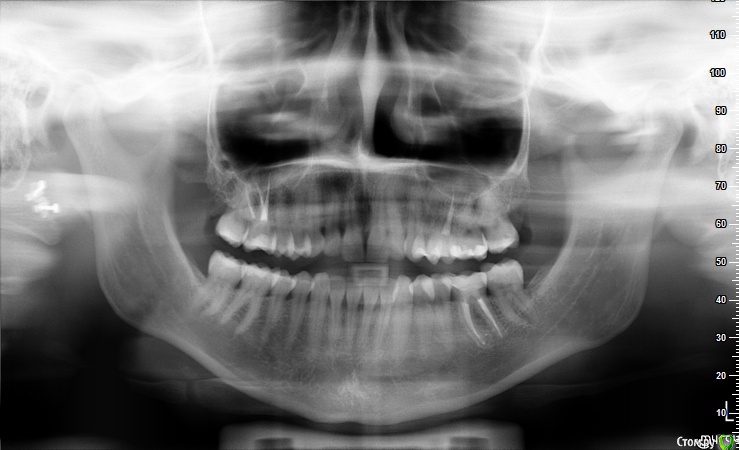

felicidade Опубликовано 6 ноября, 2015 Автор Поделиться Опубликовано 6 ноября, 2015 Здравствуйте! Это снова я Сегодня сделала контрольную ОПТГ (спустя 1г 3 мес после перепломбировки №36 и спустя 9 мес с момента последней ОПТГ). Эту не самую качественную ОПТГ я сделала вообще у ортодонта, т.к. у остальных стоматологов в нашем регионе запись новых пациентов на панорамный снимок+профилактический осмотр идёт самое раннее на январь 2016, а самое позднее - на май В общем, сейчас снова возьмусь за обзвон местных докторов, авось кто и примет меня пораньше с уже готовым снимком. А у меня, пока ищу стоматолога, снова нескромная просьба бегло оценить состояние челюсти: в апреле я наконец-то удалила верхние ретинированные зубы мудрости, ну, и, как всегда, у меня паническая боязнь вторичного кариеса под пломбами.. Всем ещё раз спасибо и хороших выходных! Ссылка на комментарий

felicidade Опубликовано 7 февраля, 2017 Автор Поделиться Опубликовано 7 февраля, 2017 (изменено) Добрый день, уважаемые господа стоматологи Вчера была на профилактической чистке зубов, заодно попросила сделать ОПТГ . Стоматолог сказал, что всё нормально - если не сложно, подтвердите или опровергните его мнение, пожалуйста Спасибо заранее! Изменено 7 февраля, 2017 пользователем felicidade Ссылка на комментарий

red_butler Опубликовано 7 февраля, 2017 Поделиться Опубликовано 7 февраля, 2017 Качество снимка не очень и сережки не сняты, но вроде все хорошо. Ссылка на комментарий